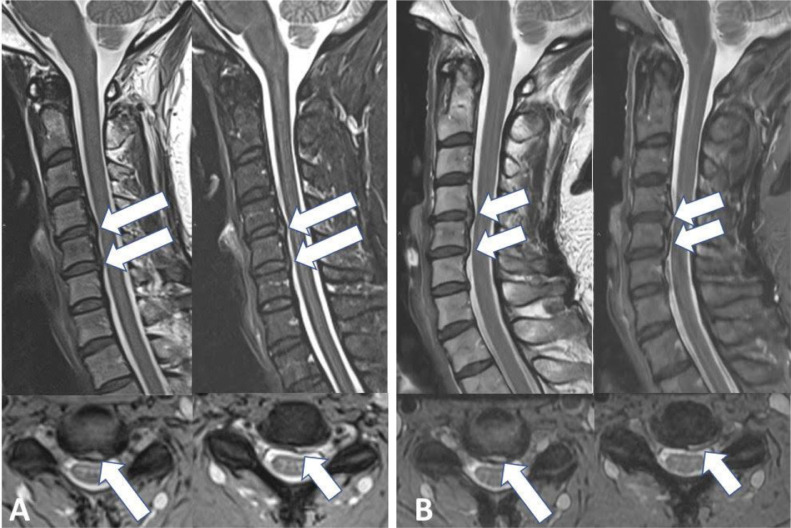

Over time, 95% (n = 104/109) of the AFs remained bright on T2WI, but showed less hyperintensity in 22% (n = 25) (Fig. 1), more hyperintensity in 10% (n = 11) or the same hyperintensity 60% (n = 66) on follow-up (Fig. 2). The remaining 5 AFs (4%) resolved completely (Fig. 3). Twenty-five cervical AFs had gadolinium enhanced evaluations, 84 were only evaluated with un enhanced studies. Only 2 (8%) of these 25 cervical AFs enhanced with gadolinium (Fig. 4). There were no instances where an annular fissure enhanced but was not bright on T2W. One of the 2 cases of enhancing cervical AF had a follow-up study with enhanced sequences. This 1 cervical AF continued to enhance.

Figure 1.

Hyperintensity on T2W of annular fissures at initial and follow-up imaging. Initial (A) Sagittal T2W TSE and Sagittal STIR images (left to right) showing central disc protrusion at levels C4-C5, C5-C6, and C6-C7 (long and short arrows) associated with posterior annular fissures at the levels C4-C5, C5-C6 (long arrow) and C6-C7 (short arrow) that appears hyperintense on T2W and STIR; (B) Follow-up of the same patient 1984 days later shown in (A) reveals unchanged multilevel central disc protrusion, reduced AF's signal intensity on T2W images with no discernible annular fissures at C4-C5 and C5-C6 (long arrow), and unchanged C6-C7 T2W hyperintense annular fissure (short arrow).

Unchanged annular fissures and disc protrusions over 252 days. Initial (A) Sagittal T2W TSE (left), Sagittal STIR (right) and Axial spoiled T2* (multiple-echo recombined gradient echo-MERGE) images (bottom) show disc protrusions associated with abnormal focal hyperintensity on T2W, STIR and MERGE images in the posterior margin of the C4-C5 and C5-C6 discs, consistent with annular fissures. (B) Follow-up imaging, Sagittal T2W TSE (left), Sagittal STIR (right) and MERGE (bottom) images reveal unchanged discs protrusions and abnormal focal hyperintensity on T2 related to annular fissures.